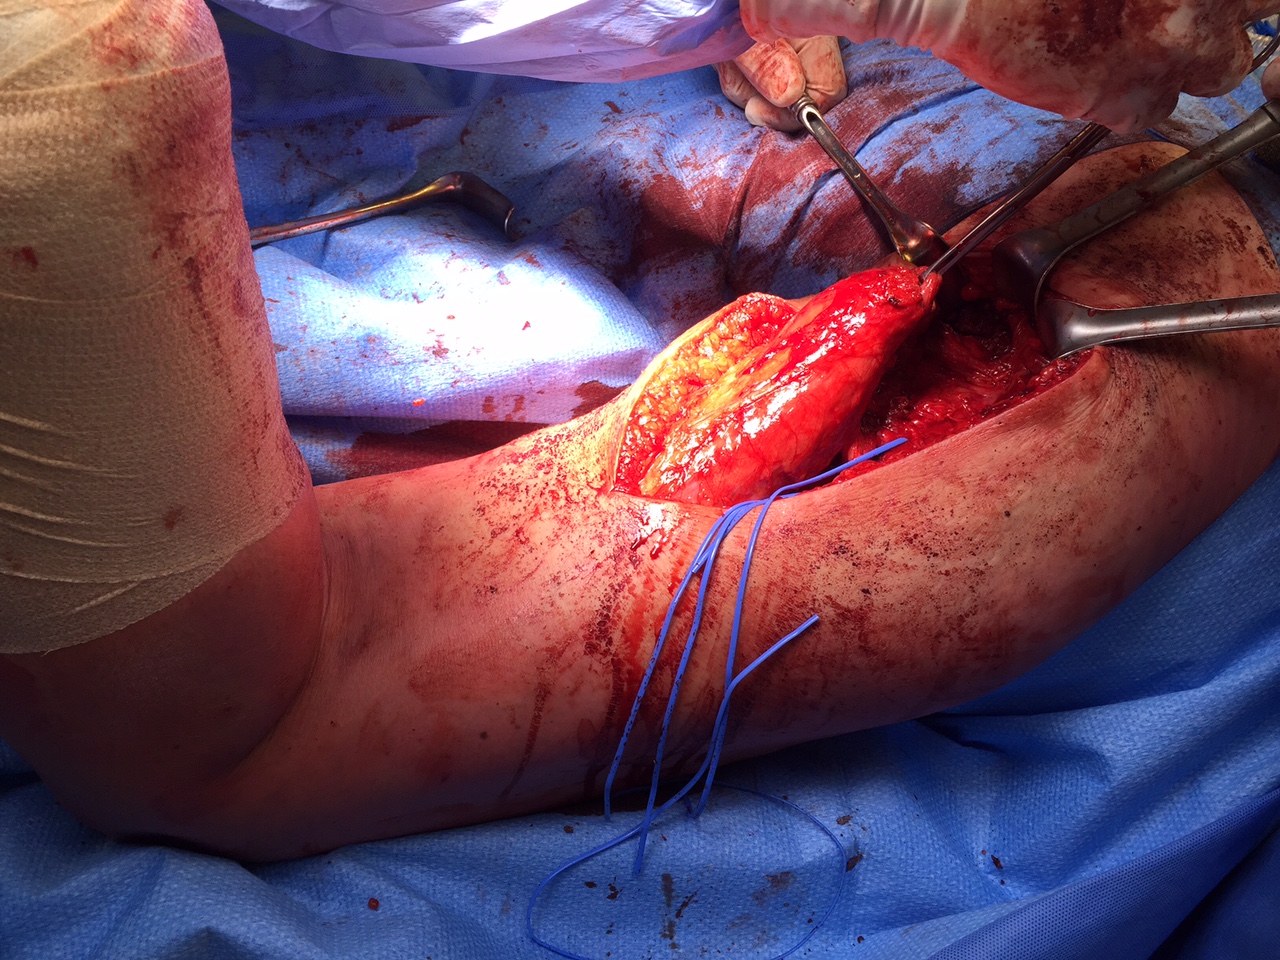

Hamstring (*) with sciatic nerve lateral to hamstring (blue vessiloop)

Identify and release proximal hamstring tendon

Stump of the conjoint tendon (*)